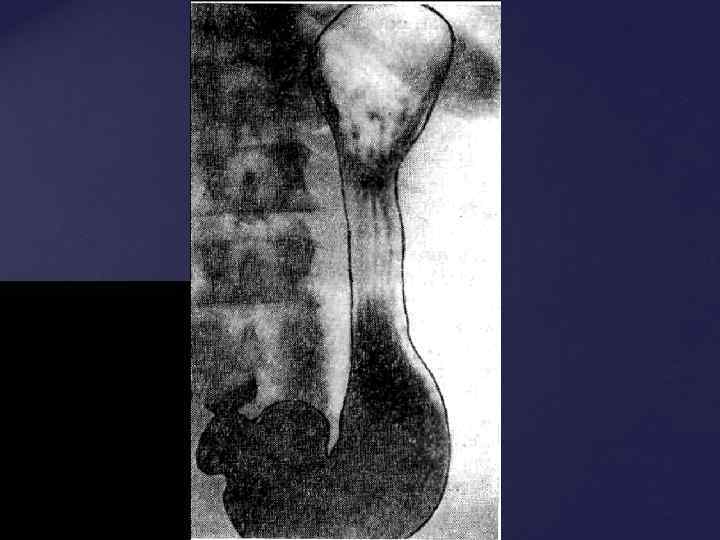

Из всех компонентов опорно-двигательного аппарата естественной рентгеновской конрастностью обладает только КОСТНАЯ ТКАНЬ (из внутренних органов – зубы). До полного окостенения (синостозирования) кости видны как бы фрагментированными из-за наличия ростковых хрящевых зон между участками уже образованной костной ткани. Знания возрастной нормы разввития костей позволяет отличить норм. ренгенологическую картину от травм и заболеваний костей.

Из всех компонентов опорно-двигательного аппарата естественной рентгеновской конрастностью обладает только КОСТНАЯ ТКАНЬ (из внутренних органов – зубы). До полного окостенения (синостозирования) кости видны как бы фрагментированными из-за наличия ростковых хрящевых зон между участками уже образованной костной ткани. Знания возрастной нормы разввития костей позволяет отличить норм. ренгенологическую картину от травм и заболеваний костей.